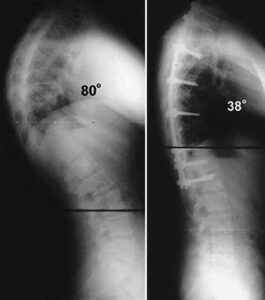

While the thoracic spine naturally curves between 20 and 45 degrees, certain postural or structural abnormalities can increase this curvature beyond normal limits. Known medically as hyperkyphosis when it exceeds 50 degrees, this excessive curvature is often simply referred to as kyphosis by doctors to describe the clinical condition resulting in a rounded upper back. The severity of kyphosis can vary. Generally, more pronounced curves lead to a more serious condition. Milder kyphosis may cause minimal discomfort or none at all, while more severe cases can result in noticeable spinal deformity, often producing a visible hump on the upper back.